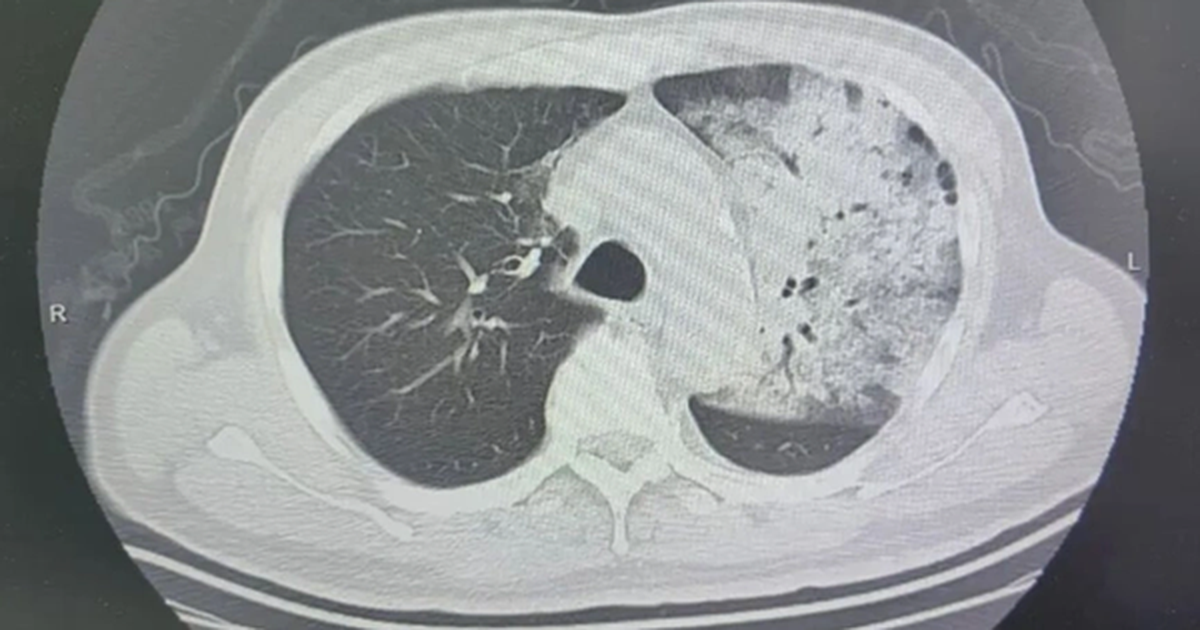

- Biến chứng thủy đậu ở người lớn gồm viêm phổi, viêm não [1].